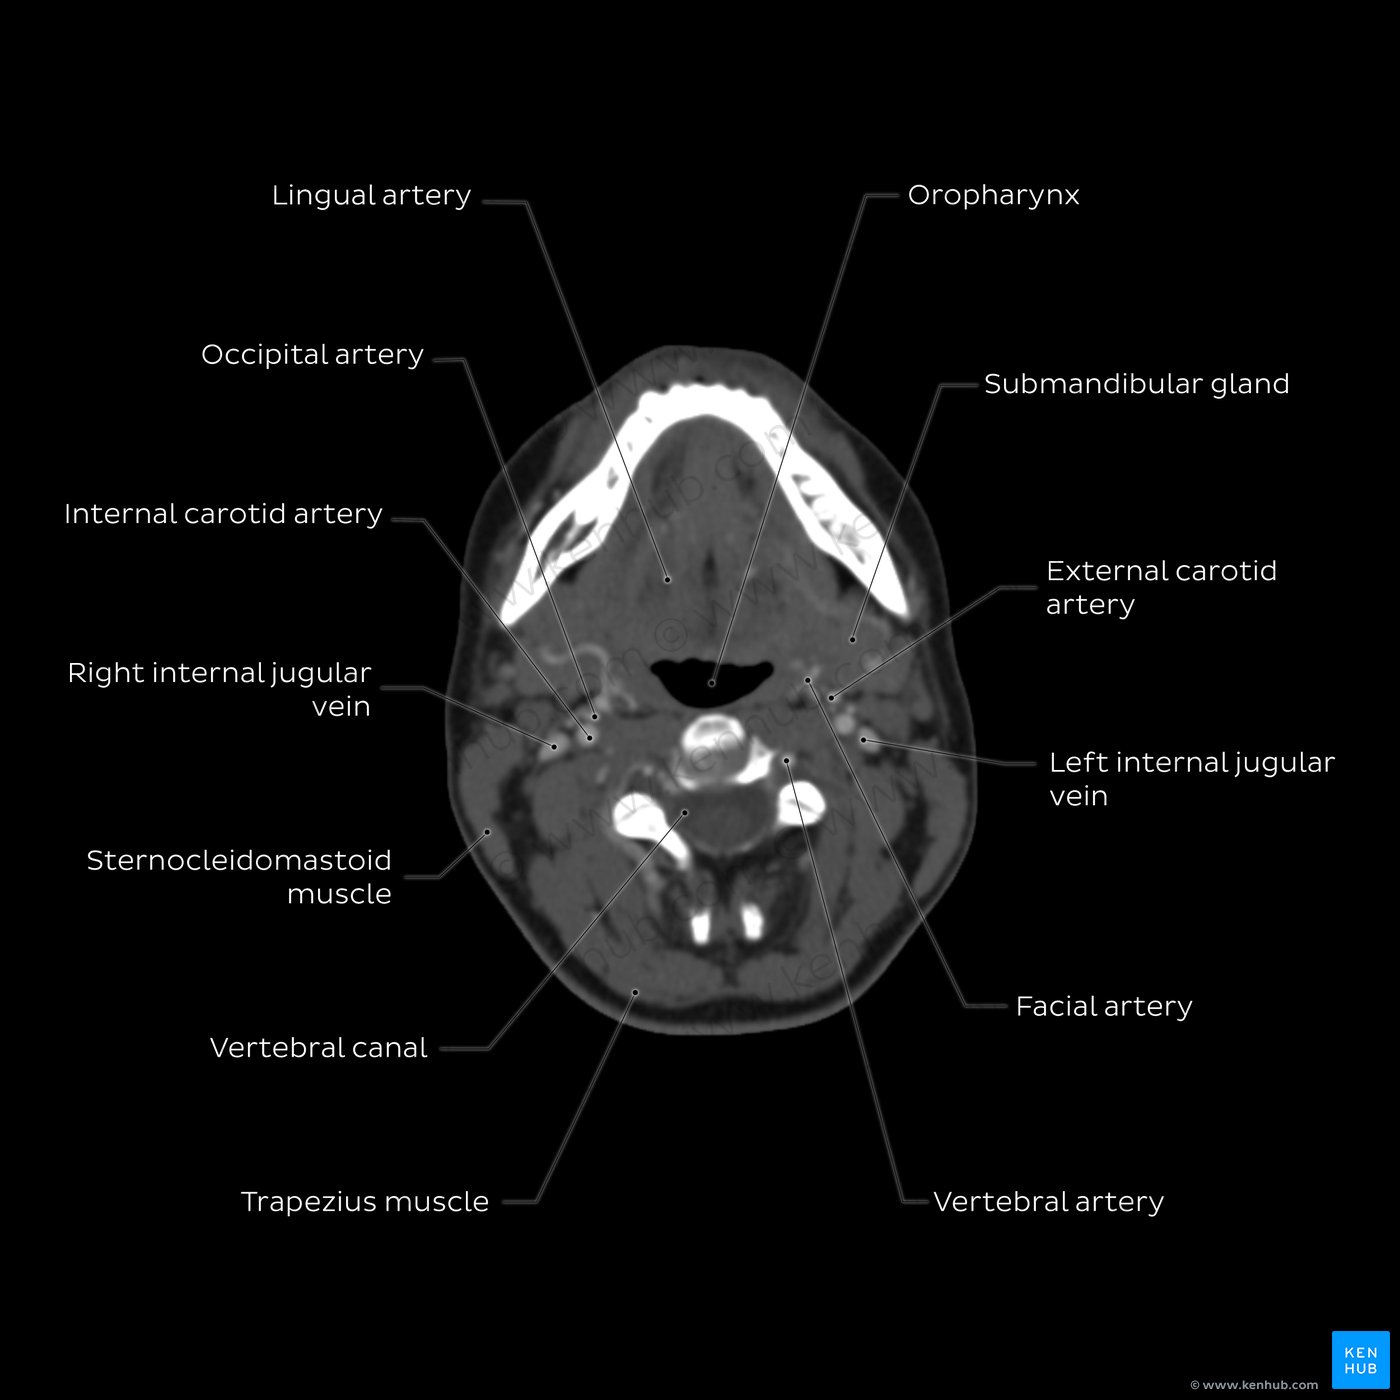

Neck (CT)

The neck is a very important region of the human body, since it is consisted of a very small space that houses several vital structures such as large arteries, organs of the airway and gastrointestinal tract and many important glands.

Axial CT scans of the neck allow us to better understand the anatomical relations of these important structures and are helpful for the identification of multiple pathological processes that can occur in that region.

The images below will show you the main structures of the neck as seen from an imaging standpoint.